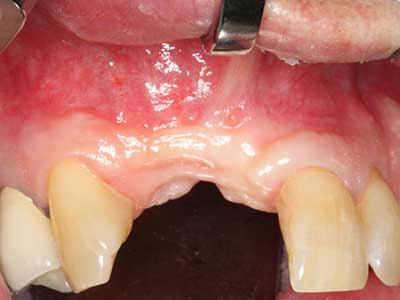

Костната тъкан е не само минерализирана структура, тя съдържа и съществено количество колагенови влакна. Това означава, че тя има не само добра компресивна сила, но и известна степен на гъвкавост, която може да се възприеме като предимство при извършване на костна аугментация. В класическата процедура по разширяване чрез костно разделяне, атрофиралият алвеоларен гребен е разделен надлъжно и внимателно разширен след достигане на подходящата остеотомна дълбочина (Фиг. 13-16), в идеалния случай без допълнително отстраняване на периостеума (Brugnami, Caiazzo et al. 2014, Stricker, Fleiner et al. 2014). Системите с винт и пластини с увеличаване на разстоянието при разширяване са доказали ефективността си при разделяне на двете костни ламели, оставайки под прага на фрактурите. В общи линии, оставащата ширина на костта от поне 3–4 mm е задължителна (Chiapasco, Zaniboni et al. 2006), за да се гарантира добра гъвкавост и достатъчно костно покритие за бъдещото поставяне на импланти. Ако е необходимо, вертикалната остеотомия на едната или двете страни може да подобри гъвкавостта. Комбинацията с допълнителни техники за аугментация, особено в букалната страна, е описана като алтернатива на класическата техника.

Процедурата по разделяне е атравматична и няма голяма загуба на пространство, използвайки пиезотриони, и няма значителна разлика между импланти в разделени челюсти и импланти в алвеоларния гребен без костен дефицит (Chiapasco, Zaniboni et al. 2006, Danza, Guidi et al. 2009). Въпреки това, важно е да има достатъчно и продължително охлаждане, особено при ограничено и дълбоко разделяне, за да се избегне термичен стрес в апикално-остеотомните зони.